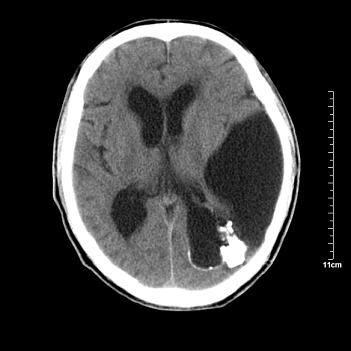

男性患者,72岁,近两天头晕来我院就诊。 因患者血压太高而未做增强,建议病人去市医院做mri检查。等得到mri随访结果再公布给大家。 测及左颞顶枕叶病灶ct值分别为5hu 30hu 729hu。

考虑左侧颞顶枕叶少突胶质细胞瘤。 今天随访患者手术病理结果 病理回报为胶质瘤2级 钙化

左侧颞顶枕叶大片状低密度影,呈均一水样密度,边界清楚,病灶边缘不规则片状钙化,左侧脑室后角扩大,中线结构未见移位,综合来看不像肿瘤,软化灶,钙化不好解释

左侧颞顶枕叶巨大囊性病灶,灶内见小片实性区且灶内及灶周围大量团块状钙化影,灶周水肿少.左侧室枕角内见环形钙化,可见较清晰前壁,钙化与室壁似有间隙.

囊变明显,钙化明显,部分实性组织,轻度占位,左侧脑室受压---考虑 少突胶质细胞瘤,畸胎瘤,寄生虫病

今天追踪患者家属手术病理结果 病理回报为胶质瘤2级并钙化

病理回报为胶质瘤2级并钙化